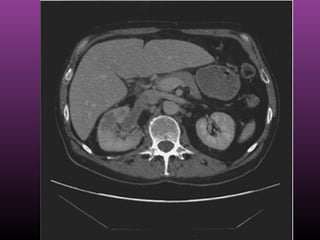

Renal Cell Carcinoma

Non contrast CT

Renal Cell CarcinomaRenal Cell Carcinoma

Contrast CT show LT renal cyst with Bosnik IV